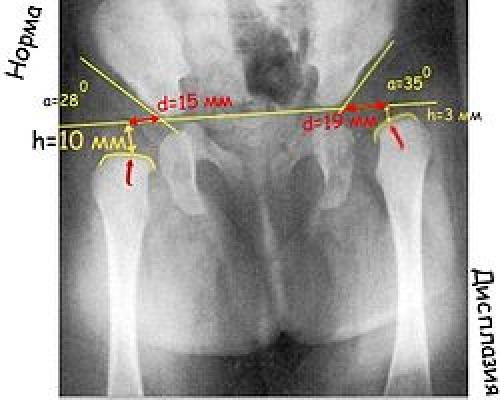

Прежде всего проводят вертикальную срединную линию, она проходит через середину крестца. Проводят горизонтальную линию через У-образные хрящи, через нижние точки подвздошной кости (линия Хильгенрейнера). Через наружно верхний край, перпендикулярно горизонтальной линии проводят линию Перкина . Часто бывает, что на стороне поражения невозможно определить верхний край вертлужной впадины. В этих случаях пользуются методом Рейнберга: симметрично, на таком же расстоянии от срединной линии проводят вертикальную линию (перпендикулярно горизонтальной). Она и будет обозначать невидимый на рентгенограмме верхнелатеральный край впадины. Через края вертлужной впадины проводят касательную линию до пересечения с горизонтальной линией Хильгенрейнера. Образованный угол называется «ацетабулярный угол», или угол наклона крыши вертлужной впадины.

Величина ацетабулярного угла в норме составляет менее 30° у новорождённых и около 20° у детей от 3 месяцев и старше.

Ацетабулярный угол, или ацетабулярный индекс — метод измерения деформации тазобедренного сустава, который характеризует угол наклона верхней части вертлужной впадины. Применяется при рентгенологическом обследовании.

Нормальный ацетабулярный индекс у новорожденного до года составляет не больше 28° . При достижении ребенком одного года и более этот показатель снижается до 22°.